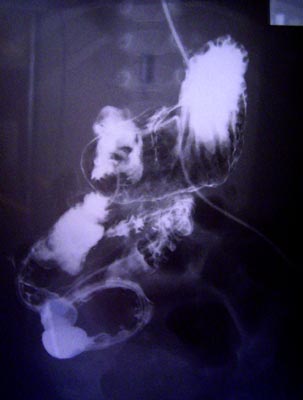

平成16年3月4日撮影。

青い線が小腸に入っているチューブ。

一カ所凄く細いところがありますが、

先生方の協議の結果、チューブを抜いても塞がることは無いだろう、とのご判断。

下の写真と比べ、本当に腸らしく太くなっているのがわかります。

ただ、圧倒的に長さが足りないことは、どうしようもありません。小腸がより太くなり、その表面のヒダが毛足の長い絨毯のようになり、少しでも表面積を増やすよう、対応してくれることを祈ります。

平成15年11月27日撮影。

死にかけていた部分の小腸が、本当に細い。

上の写真と同じく青のラインがチューブであるが、細い部分は黄色く色分けしてみました。

もう、チューブの回りにかろうじて腸が残っている感じ。黄色の上下は元気な小腸なので、太さの違いは一目瞭然です。

この写真を見せられた当時は、落胆せざるを得えませんでした。

しかし、「腸とて筋肉!使えば必ず太くなる!」信じることにしました。しかし見事回復してくれました。